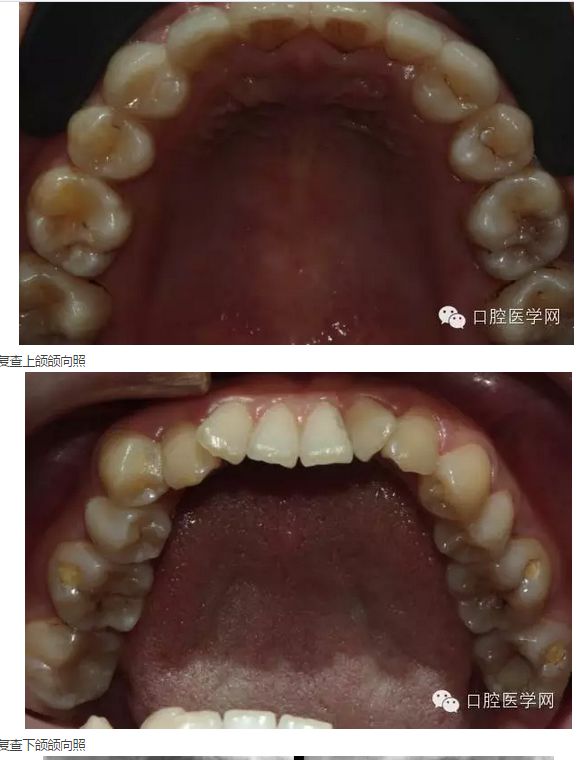

2015年5月3日:戴牙。(見圖24-30)(拍照時22、24排齦線尚未取出)